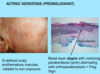

A: [Actinic Keratosis] is a precursor to ______

B: Tx (2)

A: [Actinic Keratosis] is a precursor to [Squamous Cell Carcinoma]

B:

- Cryotherapy

- Topical tx

A: Describe Histology (3)

B: Dz

C: What’s the primary leukocyte in the skin

A: image

-Solar Elastosis=Grayish-bluish color of the Dermis from sun damage

B: [Actinic Keratosis-PreMalignant]

C: Lymphocyte